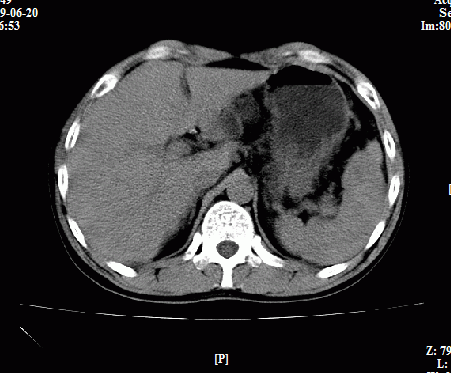

以下是引用随光逐影在2009-6-23 11:37:00的发言:[br]1)考虑胃癌;建议行胃镜检查进一步明确诊断。2)肝右叶肝内胆管结石(或钙化)。

以下是引用zxl51642在2009-6-23 11:31:00的发言:[br]胃大弯侧壁明显增厚呈软组织肿块,考虑胃癌可能性大,建议胃镜活检。